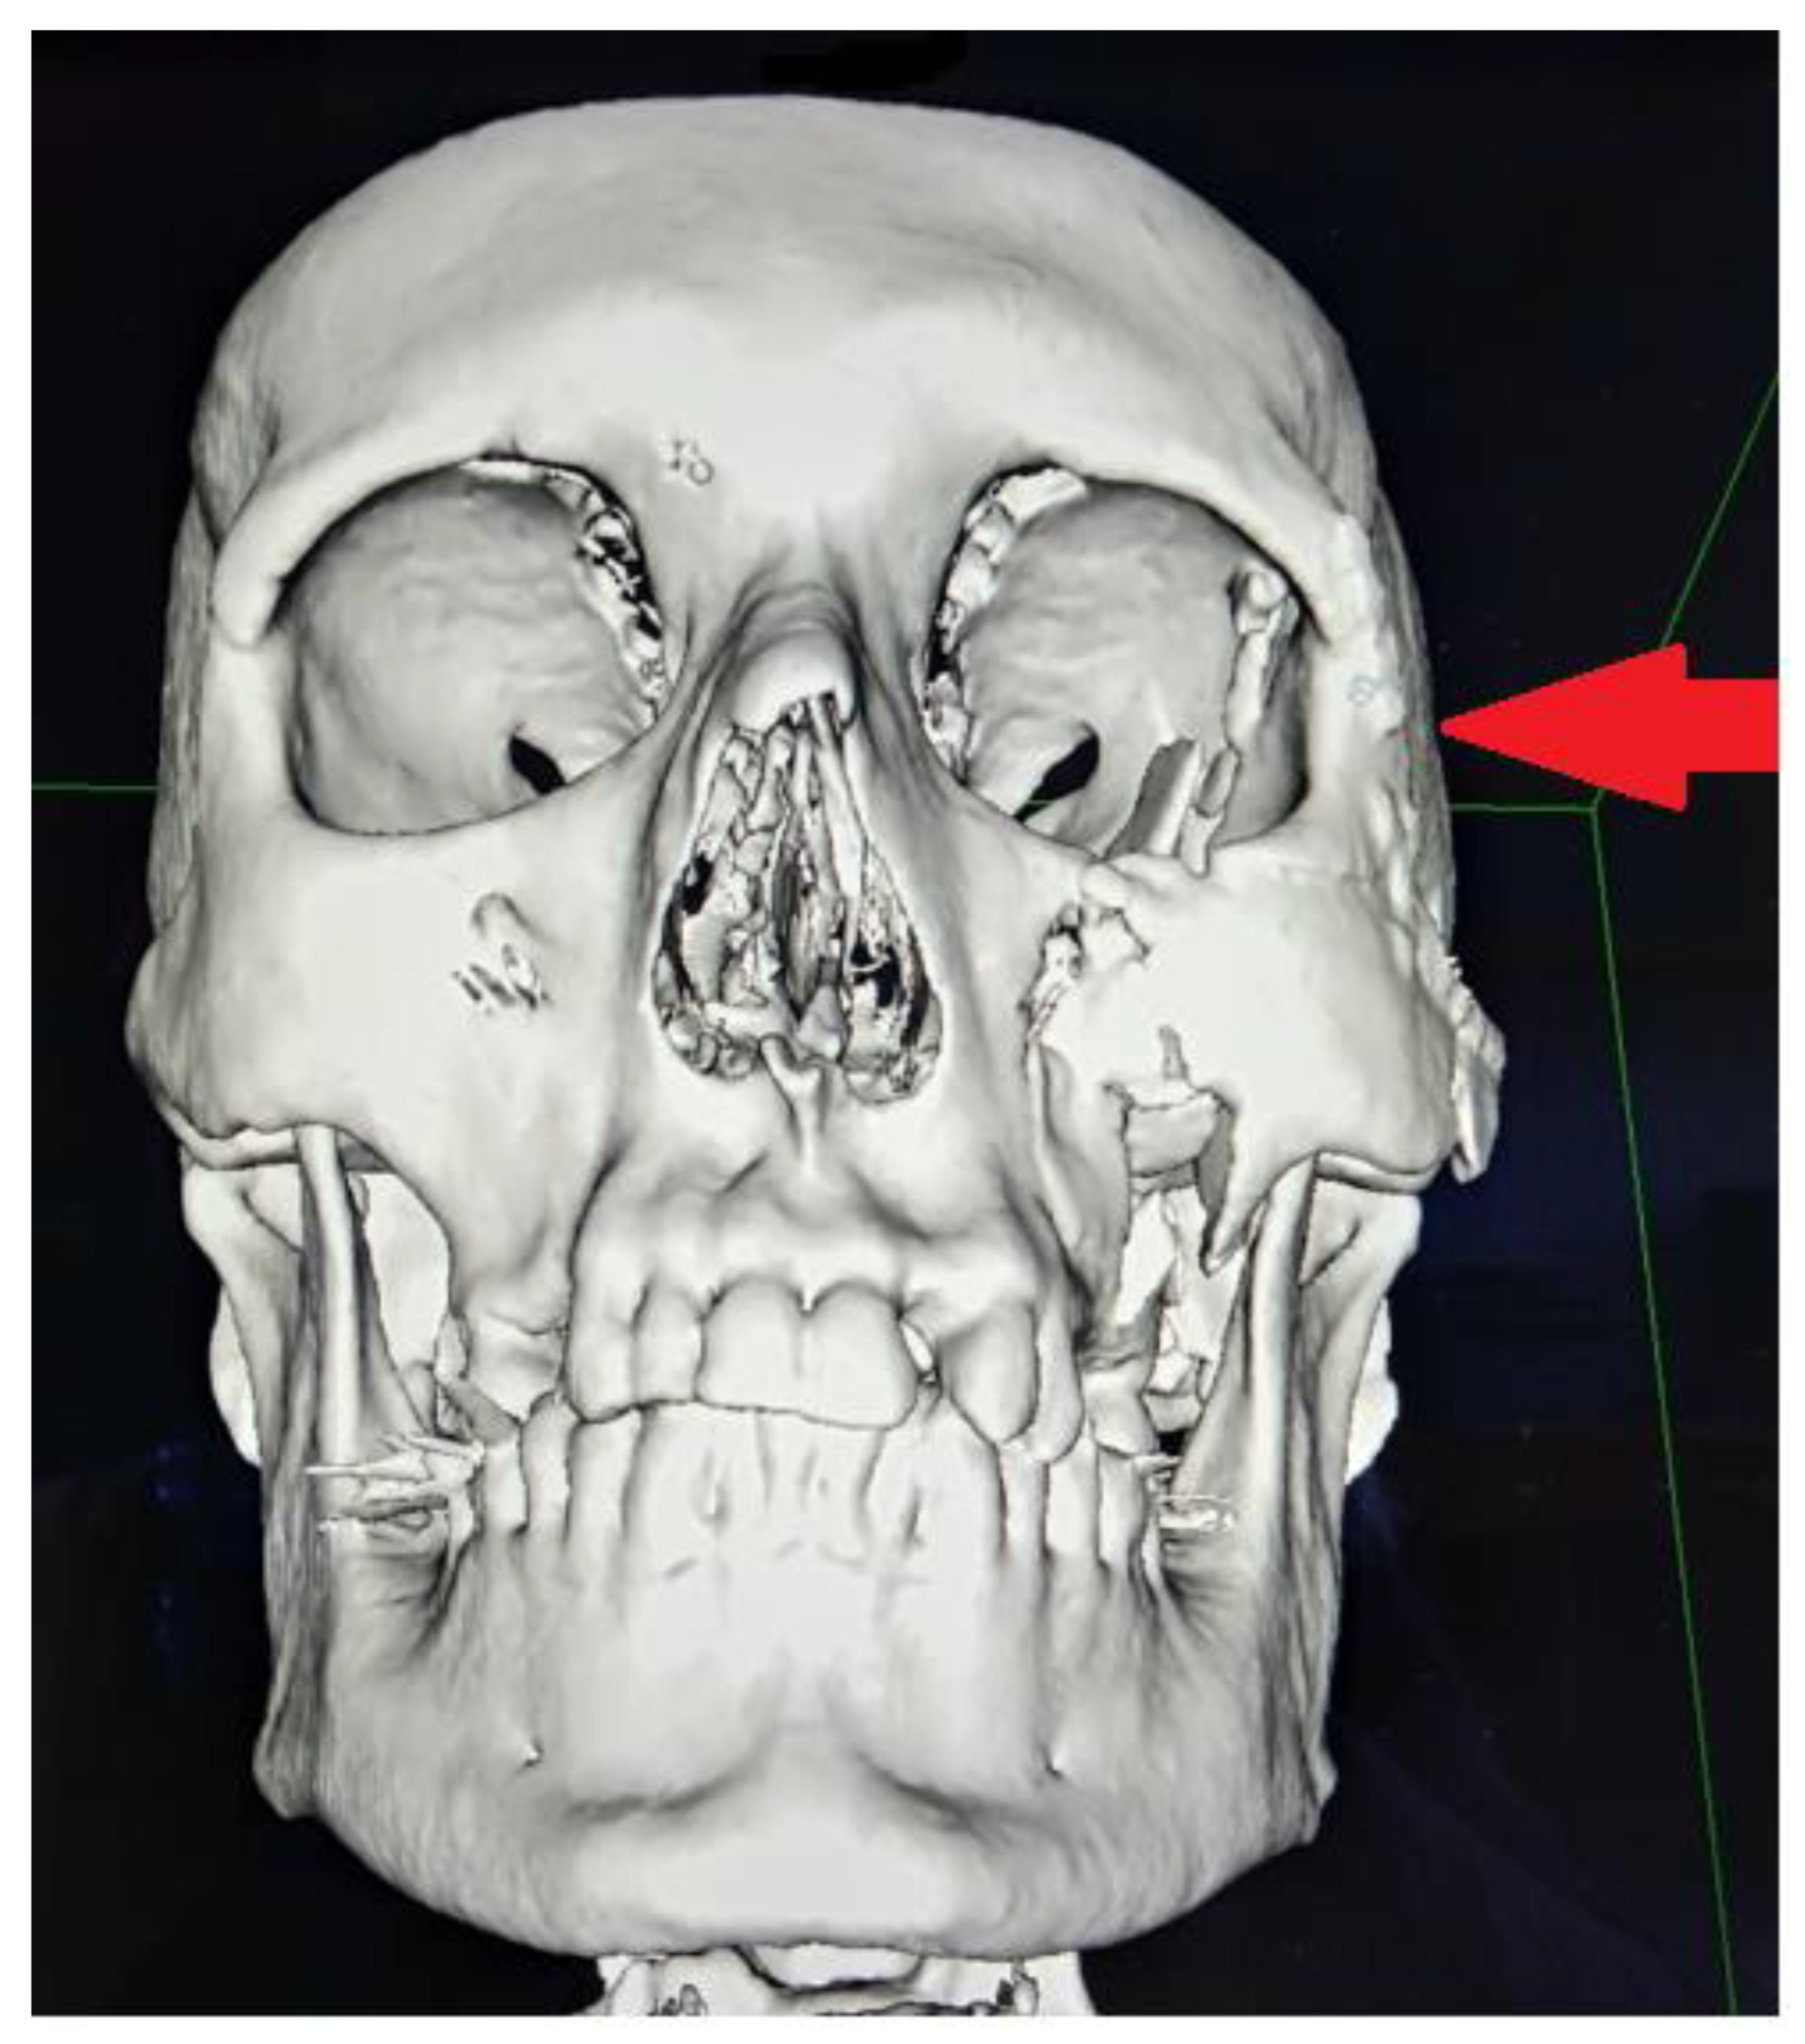

Figure 4. A frontal view on reconstruction from a 3D-CT trauma scan of the major cranio-facial fractures on the left orbital and zygomatico-malar complex area.

Figure 5. Three-dimensional reconstruction of the fractured area. The red arrow marks the entirely preserved frontal area. The major impact force was focused on the left orbit, zygomatic, and temporal bone areas. Green arrows indicate the fracture lines at the zygomatico-temporal suture, zygomatic bone, prominence with arch, anterior part of the maxillary sinus wall, lateral wall of the left eye socket, inferior border of the left orbit, and the temporal bone. No zygomatic bone-coronoid process of the mandible conflict was present.

Figure 6. The major scope of 3D-reconstruction is focused on the decreased volume of the left orbital socket because of the degree of bone displacement towards the eye socket (red arrow). No zygomatic bone-coronoid process of the mandible conflict was present.